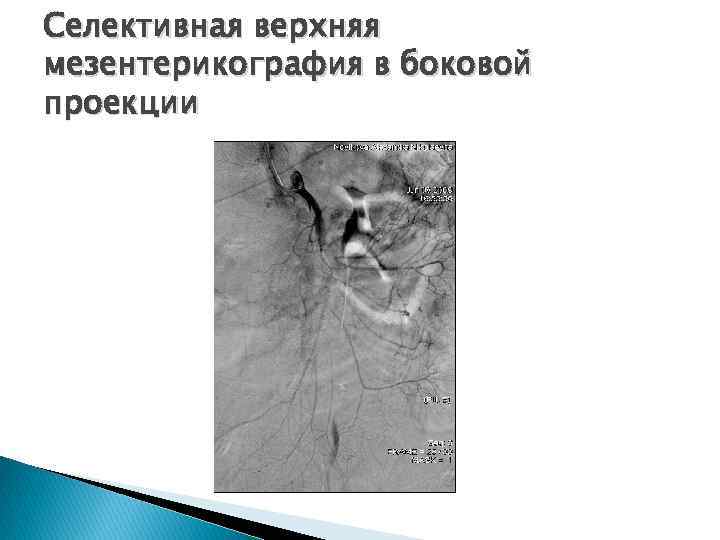

Селективная верхняя мезентерикография в боковой проекции

Селективная верхняя мезентерикография в боковой проекции